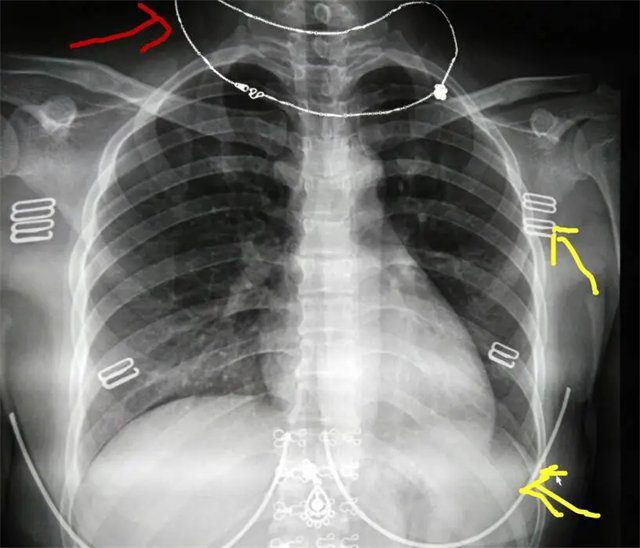

缺陷:雙側(cè)胸鎖關(guān)節(jié)不對(duì)稱,且有手機(jī)顯影。

解決:去除手機(jī)后,使患者左側(cè)緊貼成像件曝光。